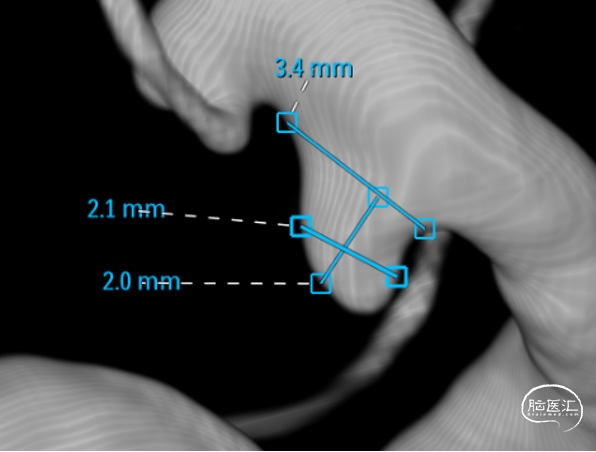

微导管3D评估动脉瘤与载瘤动脉关系

WEB选择:理想SL9x3(没有),选择SL8x4

直接测量:7.4x3.92mm

3D测量:7.22x5.35mm

对比测量:8.9x4.8mm(偏大10%)